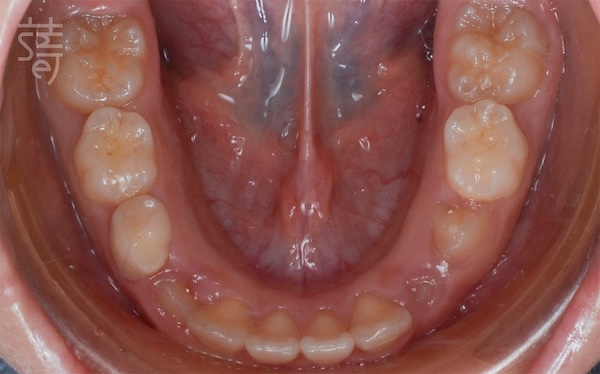

兩年後回診,X 光片上清楚顯示小緹的牙列變整齊了、牙弓更開展,嘴型也能自然閉合。那些早期努力的累積,就這樣安靜卻確實地發生在孩子身上。

Two years later, Ti returned for a follow-up, and the X-rays told the story clearly: a broader arch, straighter teeth, and a relaxed, natural lip seal. The quiet, steady work of early treatment had taken root.

媽媽笑著分享:「兩年間小緹改變很多,慢慢長出自信,各種場合總能自在露齒笑!」她很慶幸自己在孩子的早期階段,做了這個正確的決定。

Her mother put it simply—Ti was still shy, but she carried herself with more ease, smiling freely in a way that felt new and self-assured.